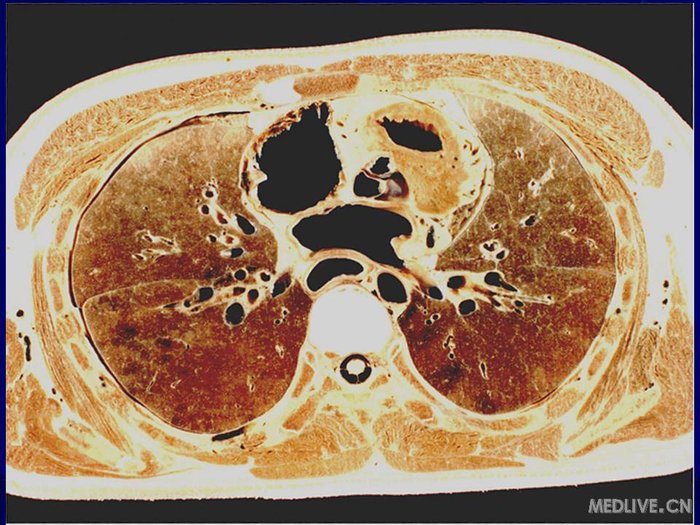

肺门层面

肺门层面,肺门

肺门和肺段断层解剖及ct

右上叶支气管平面:右肺门可 见右主支气管,右上